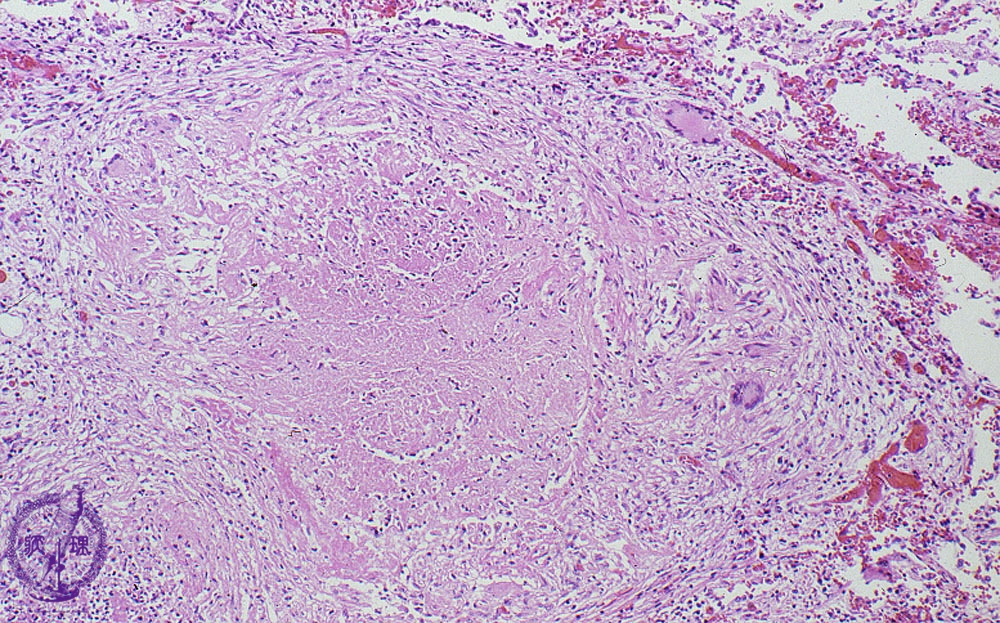

Как прогрессирует саркоидоз: что происходит на тканевом уровне

На тканевом или клеточном уровне прогрессирование болезни саркоидоза можно разделить на три фазы:

- Первое видимое изменение — воспаление.

- На второй стадии формируются гранулемы. Гранулемы представляют собой образования или узелки в хронически воспаленной ткани и являются классическим признаком саркоидоза. Гранулемы — это попытка организма отгородить или изолировать организмы и другие инородные частицы, которые иммунной системе трудно уничтожить или избавиться от них.

- В третьей фазе происходит фиброз (рубцевание) тканей или органов. Если рубцы обширны в жизненно важном органе, саркоидоз иногда приводит к летальному исходу.

У некоторых людей болезнь переходит от одной фазы к другой в тканях пораженного органа.В других случаях разные фазы тканевых изменений происходят в одном и том же органе одновременно. У многих пациентов с саркоидозом гранулемы проходят сами по себе через 2–3 года, при этом пациент ничего не знает и ничего не предпринимает. В других случаях гранулемы прогрессируют до необратимого фиброза. Изменения иммунной системы, которые позволяют заболеванию одного человека прогрессировать, в то время как болезнь другого человека проходит, недостаточно изучены и продолжают изучаться.

Альвеолит либо проходит сам по себе, либо прогрессирует до образования гранулемы. Образцы легочной ткани могут показать наличие гранулем.

Гранулемы в легких могут привести к сужению дыхательных путей, увеличению лимфатических узлов в грудной клетке, а также к воспалению и рубцеванию (фиброзу) легочной ткани.Рубцевание приводит к тому, что легочная ткань становится жесткой и разрушает воздушные мешочки, затрудняя дыхание.